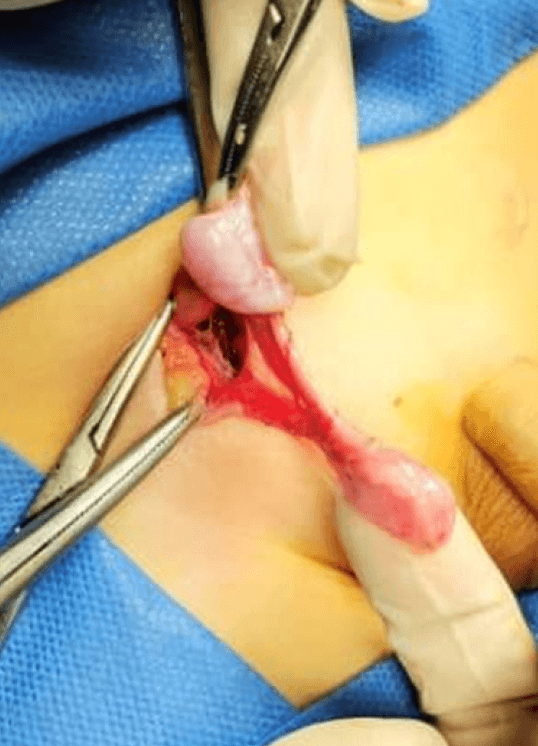

En el examen físico se corroboró la presencia de un testículo en el canal inguinal, y una ecografía doppler mostró un testículo izquierdo en la región inguinal de buen tamaño y con vasculatura conservada. Durante la cirugía, se encontraron los siguientes hallazgos: un testículo con abundante fibrosis, de difícil disección, que pudo ser fijado en el hemiescroto correspondiente. Además, se identificó una estructura de menor tamaño con características testiculares y buen aspecto, localizada en el hemiescroto izquierdo. (Fig. 1,2) Se decide no realizar la exeresis de esta estructura y se fijó en dicho hemiescroto, (Fig. 3) manteniendo una conducta expectante.

Figura 2. Hallazgos de la cirugía, compatible con tipo 2.